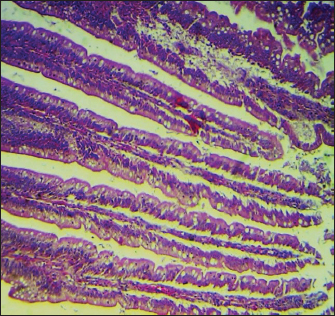

Histopathological study

The results noted in Figures 15 showed that chicks infected with S. enteritidis had edema among the muscular layer with atrophy of some intestinal villi. On the other hand, broilers infected with S. enteritidis and treated with C. myxa showed degeneration of intestinal glands with extensive inflammatory cell infiltration also mild sub-muscular edema, while with curcumin-treated group showed normal intestinal villi architectures, with hyperplasia of intestinal associated lymphoid tissue. The result noted a clear improvement in broilers that received C. myxa and curcumin showing normal intestinal villi with an increase in the number of goblet cells. The data of the present study confirmed the effectiveness of C. myxa and curcumin and especially the synergistic action between them in inhibiting the growth of S. enteritidis bacteria in poultry chickens, improving antioxidants and reducing free radicals, in addition to its action as a good anti-inflammatory at the blood level and suppressing the levels of cytokines that encourage inflammation and its role in improving intestinal tissues and making them close or similar to the health of broiler.

Fig. 3. Cross section of the intestine of poultry infected with S. enteritidis and treated with C. myxa, showing degeneration of intestinal glands with some inflammatory cell infiltration also mild sub-muscular edema (200×, H & E).